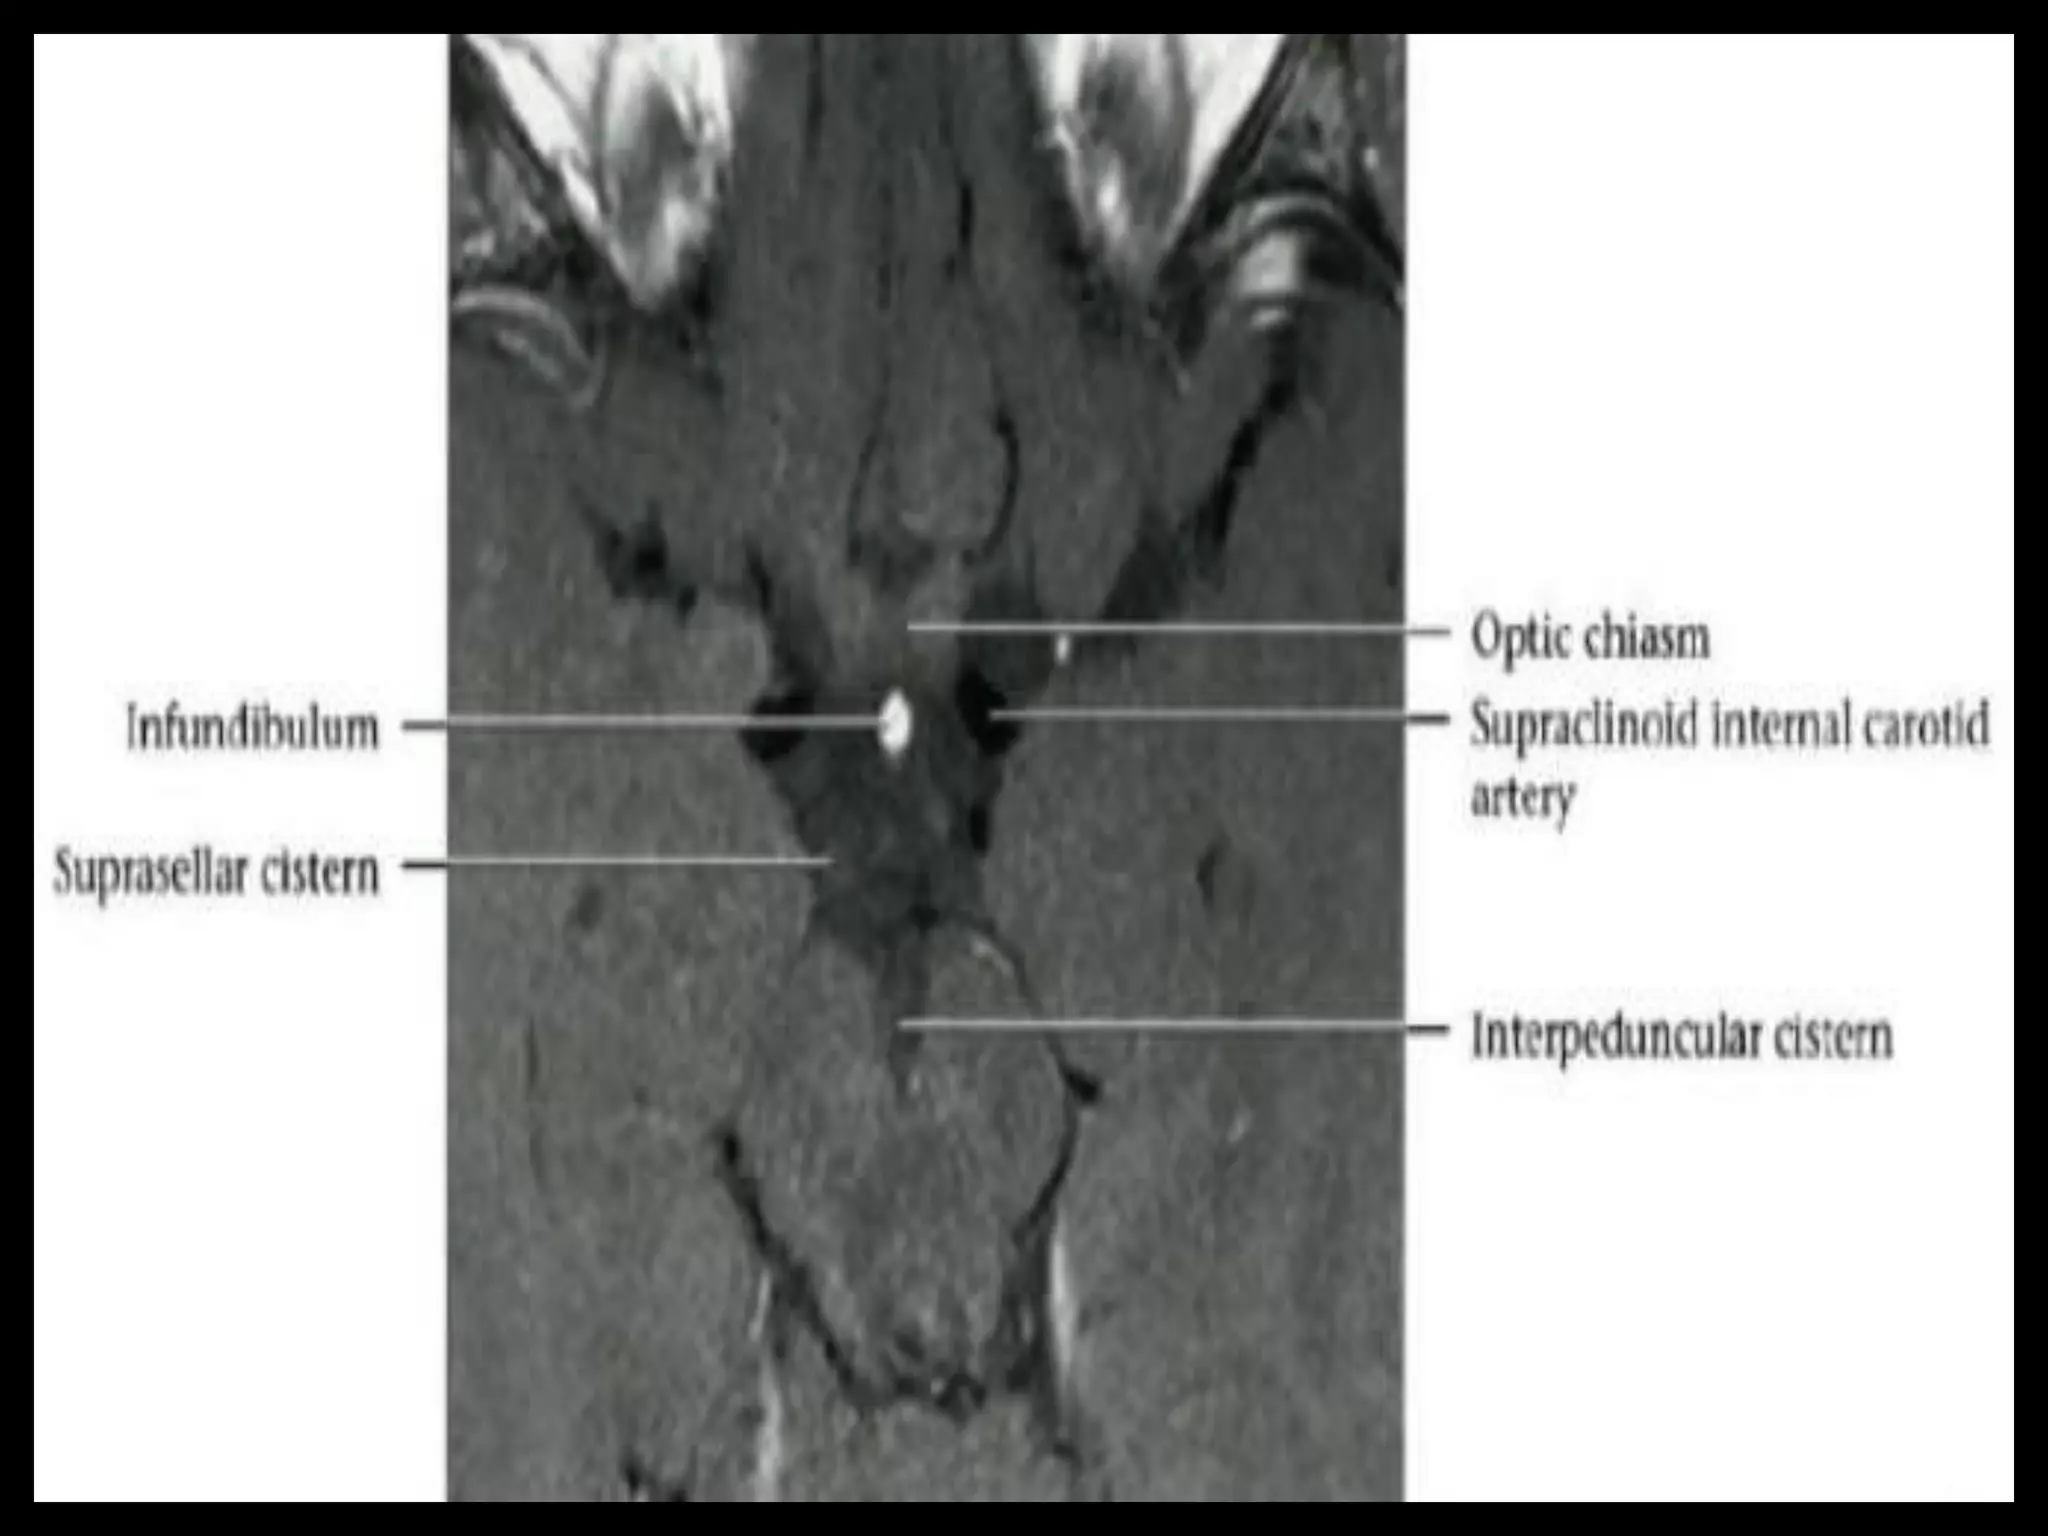

Suprasellar Cistern AndOptic Apparatus.